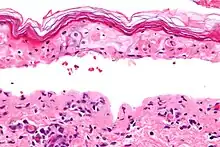

Patología

El síndrome, al igual que la necrólisis epidérmica tóxica y el eritema multiforme, está caracterizado por la confluente necrosis epidérmica con la inflamación mínima asociada. La agudeza es evidente observando el patrón de la capa córnea.

Desde el punto de vista patológico, el hallazgo más característico es la necrólisis epidérmica, espongiosis, edema intracelular, cambios vacuolares en la unión dermoepidérmica, edema y extravasación de eritrocitos. La biopsia de piel puede confirmar el diagnóstico.